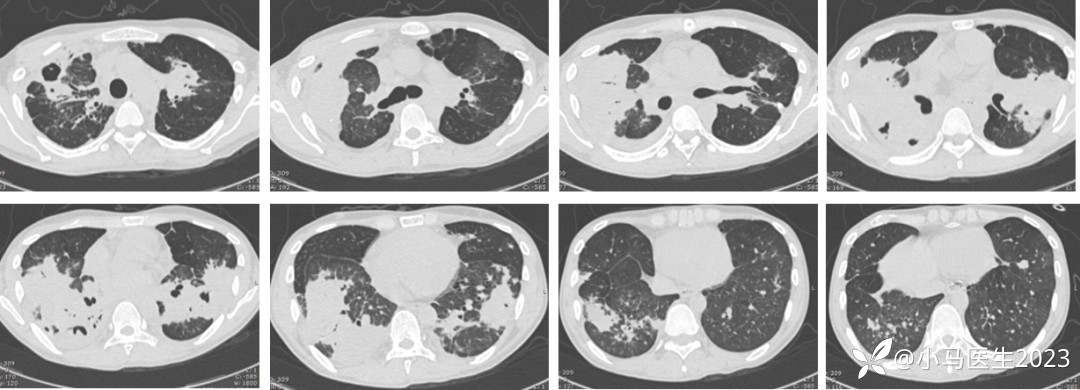

停用激素后病灶增多

03-29复查胸部CT进展

胸部CT对比